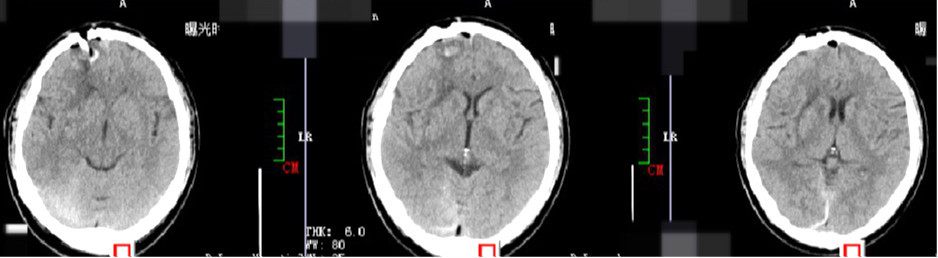

术后第一天

术后第1天